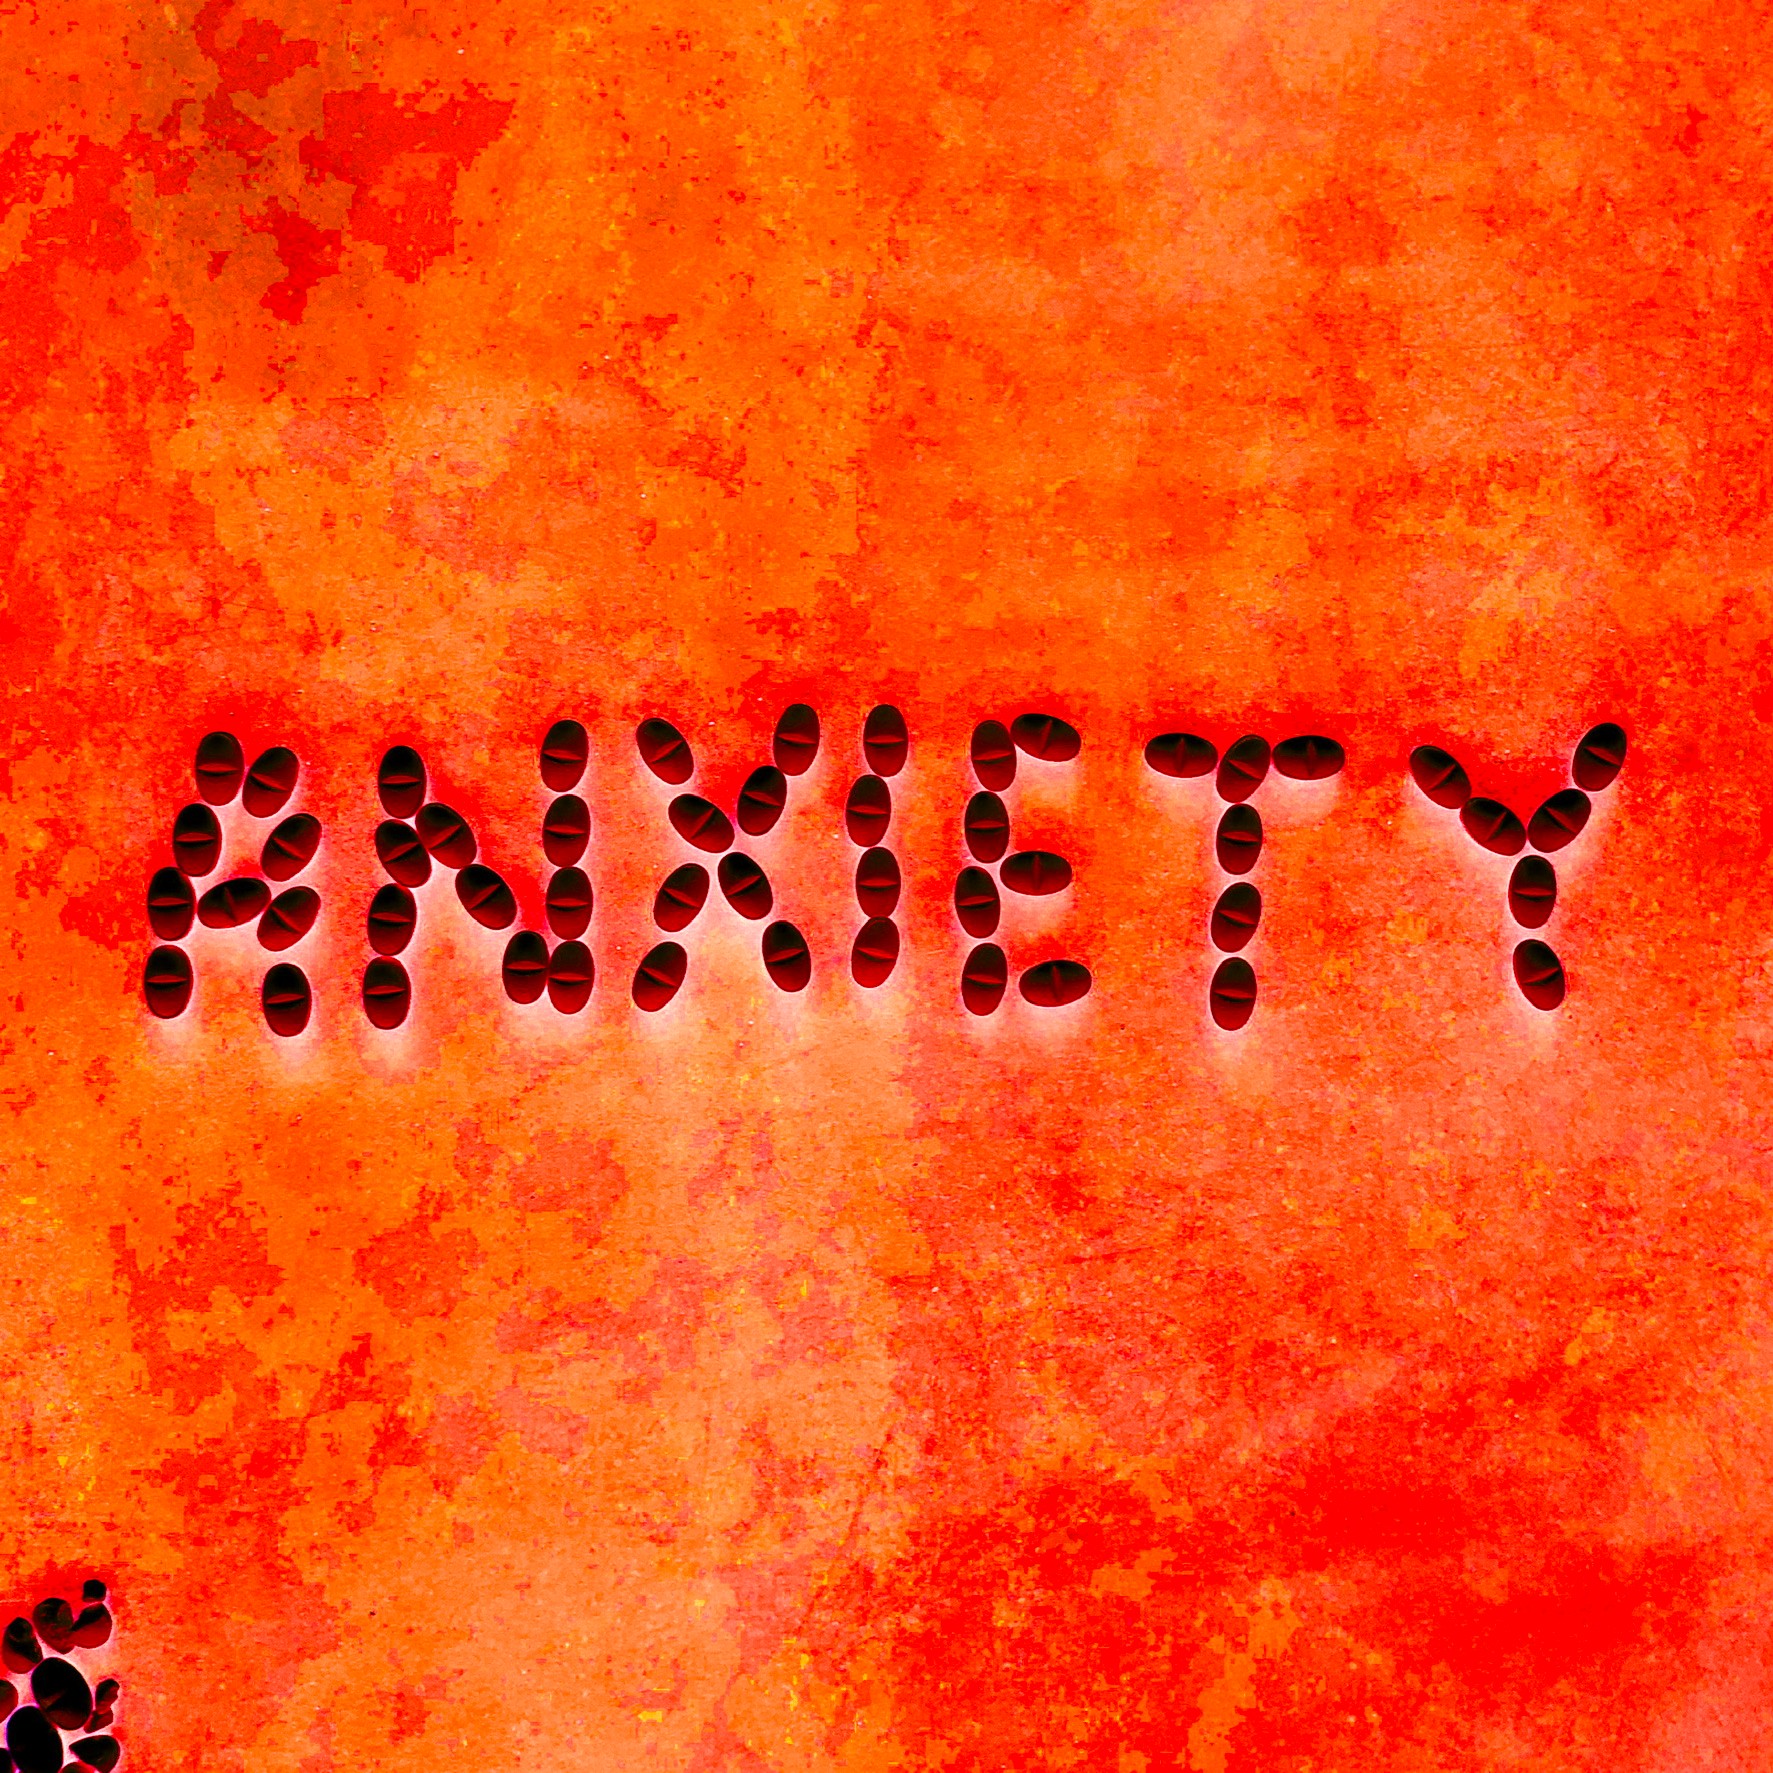

In my frustration I dumped a bunch of those pills out they were pretty, I snapped a pic. The meds I was to discontinue got their farewell by being crushed, I took a pic. I liked it, it made me feel like something other than a patient. I spelled out symptoms with their corresponding pills, sometimes taking hours more pictures.

I had wanted to be one of those cool artists that did photo diaries or Vlogs of the whole illness. I was far too out of it, between the pain and the meds, to even think about doing something like that. With help, I began digitally manipulating them to make them more colorful and textural, it gave me hope amidst the mess.

I was hurting and it helped. Aren’t we all hurting? Each person has their own mess to deal with. Many stop to take a picture of something that causes a stir in them. I want to share what gave me hope through the web of treatments, trauma, and a myriad of medication.